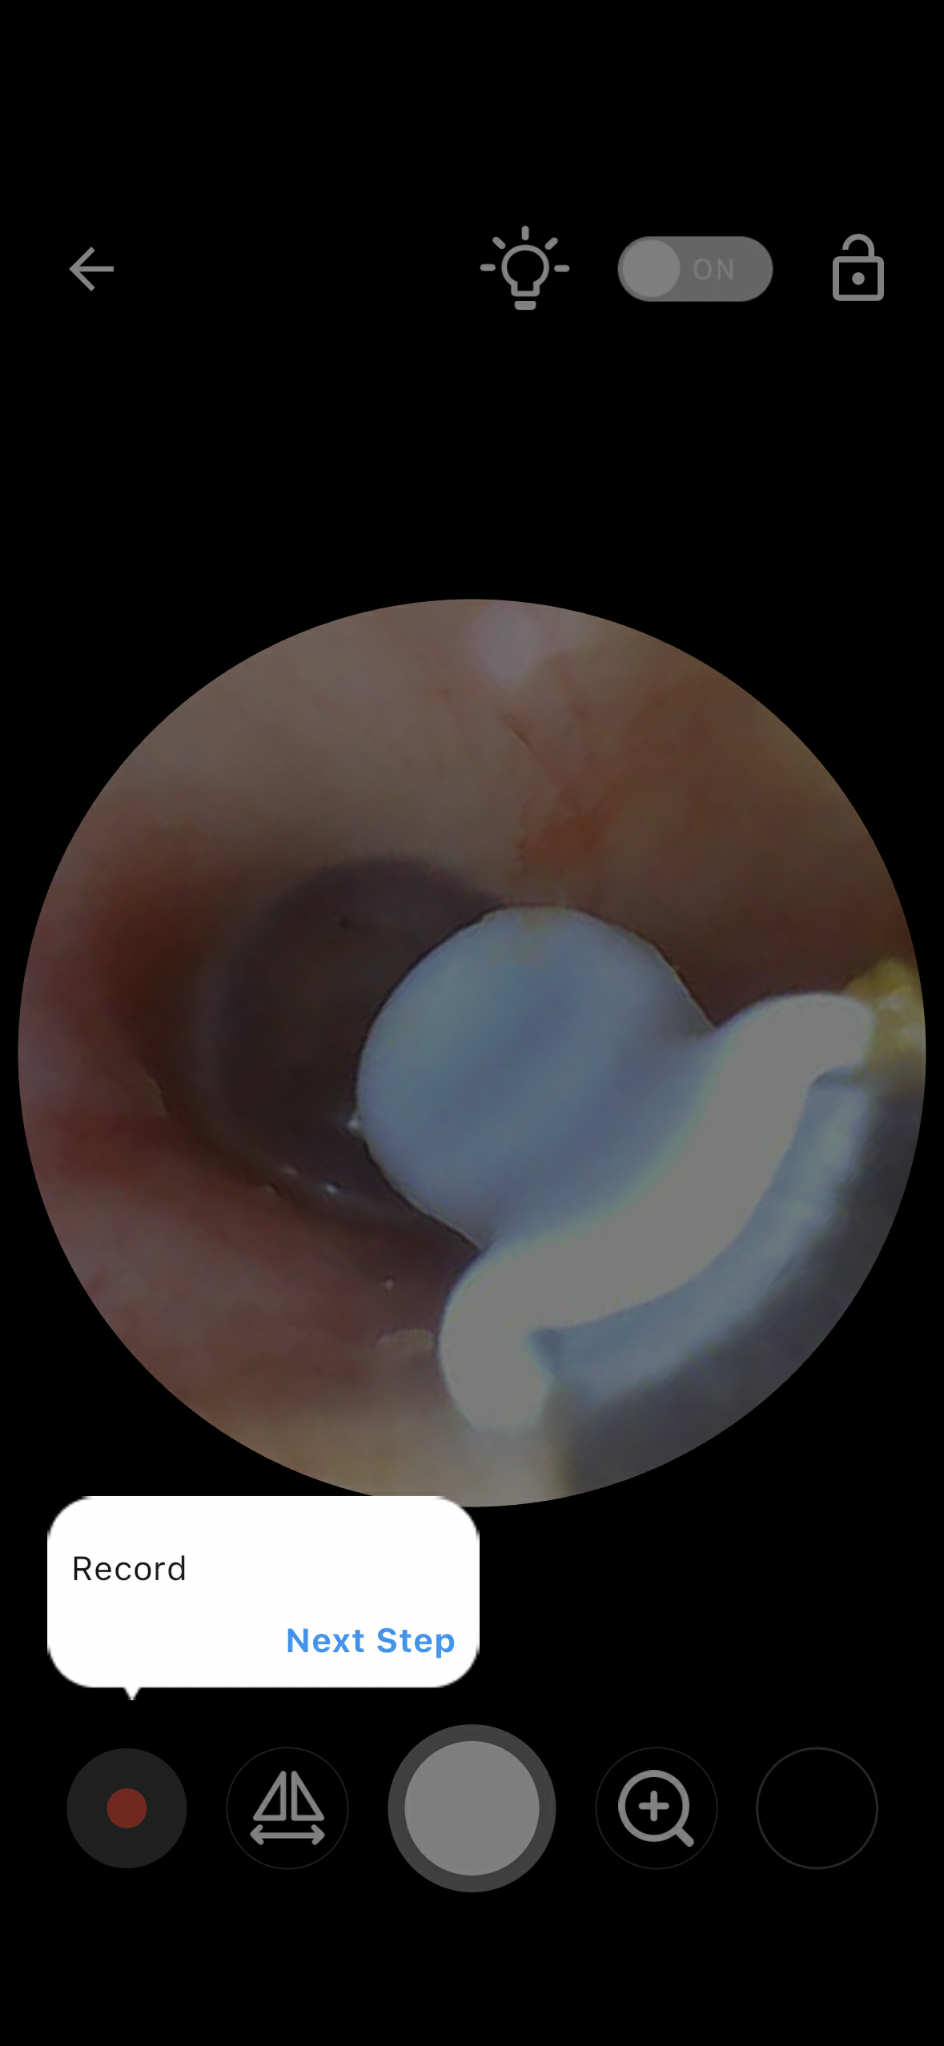

ภายในหูเป็นแบบนี้ปกติไหม

เรามีน้ำไหลออกจากหูตอนตื่นแต่ไม่ทุกครั้ง ตอนกินอาหาร ผลไม้ต่างๆเป็นช่วงต้นปีจนถึงตอนนี้ แต่มาทำงานได้เกือบเดือนต้องใส่แมสแล้วมันปวดหูมากกกปวดด้านนอกด้านในแก้วหู พึ่งได้ไปหาหมอแต่ไปห้องฉุกเฉินหมอบอกว่าปกติแต่ถ้ามีอาการอีกแนะนำให้ไปหาหมอหูเฉพาะทาง แต่อันนี้คือปกติมั้ยนะ(ส่องเองเอารูปให้หมอดูแล้ว)เหมือนมีน้ำข้างในหรือทุกคนก็เป็นแบบนี้คะ